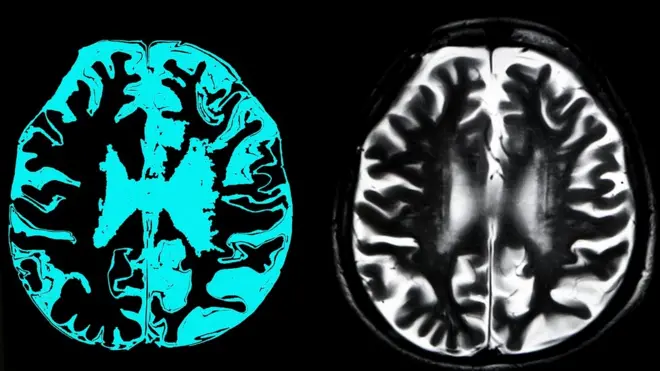

Međutim, kako je pokazao eksperiment koji su sproveli britanski naučnici, ova bolest se može prilično precizno dijagnostikovati na osnovu rezultata jedne studije - magnetnom rezonancom (MRI) mozga.

Istina, uz jedan važan uslov: slike ne treba da proučava i analizira neurolog, već mašina koju je on obučio.

Tačnije, veštačka inteligencija.